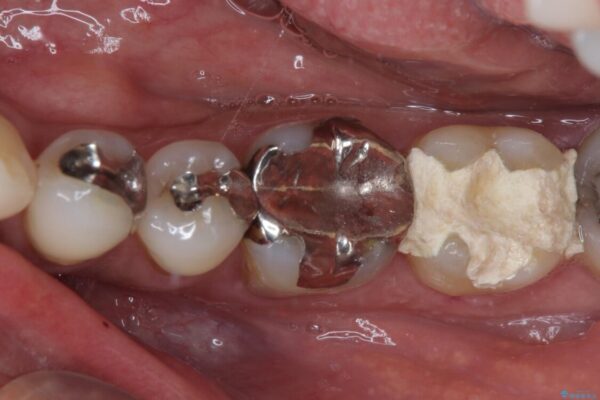

神経組織を部分的に除去することが分かっていたため、ラバーダムなどの環境を整え、無菌的環境下にて処置を進めて行きました。

虫歯は深くまで進行しており、歯冠部の神経から出血が認められました。神経を部分的に除去したところ出血が治まったので、生体親和性の非常に高いセメントにて充填し、仮封をしました。

後日状態を確認したところ、残された神経に異常は認められませんでした。

治療途中

• 治療をしても違和感の続く奥歯 神経を極力残した虫歯治療 治療途中画像